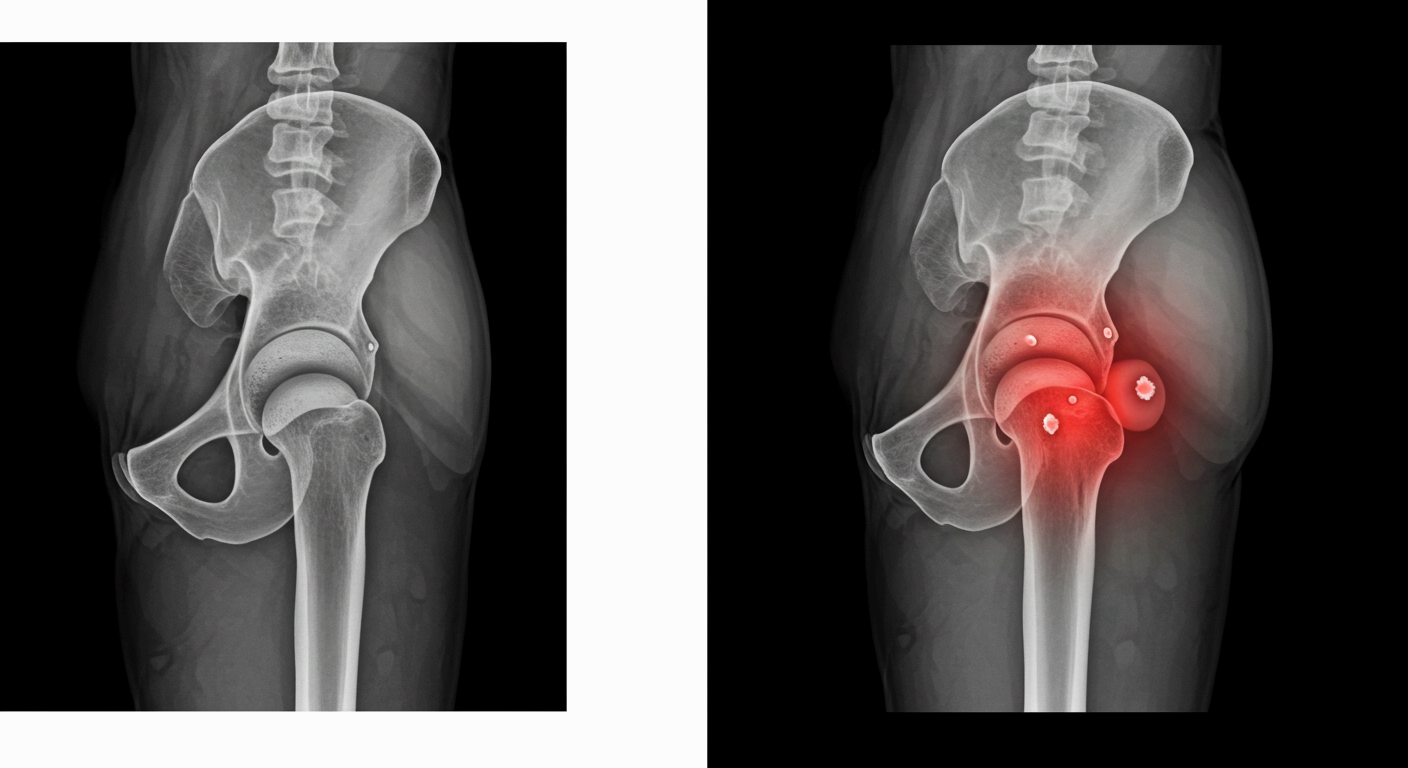

고관절 통증 증상, 이렇게 나타납니다

고관절 통증은 단순히 엉덩이 부위만 아픈 것이 아니라, 사타구니·허벅지·엉덩이·무릎 등 여러 부위로 연관 통증이 나타나는 복합 증상입니다.

고관절 통증 원인, 왜 아픈 걸까요?

📌 고관절 충돌 증후군 (FAI)

- 대퇴골두와 비구가 부딪히는 구조적 이상으로 통증 유발

📌 퇴행성 고관절염

- 고관절 연골이 닳아 없어지며 뼈와 뼈가 직접 마찰됨

📌 고관절 점액낭염

- 고관절 부근 점액낭에 염증이 생기며 눌렀을 때 통증이 심함

📌 대퇴골두 무혈성 괴사

- 혈액 공급 부족으로 뼈 조직이 괴사되어 통증 유발

📌 고관절 이형성증

- 선천적으로 고관절의 형성이 불완전하여 관절 불안정과 통증 유발

- 유아기에 진단되는 경우도 많고, 성인기에 퇴행성 질환으로 이어질 수 있음